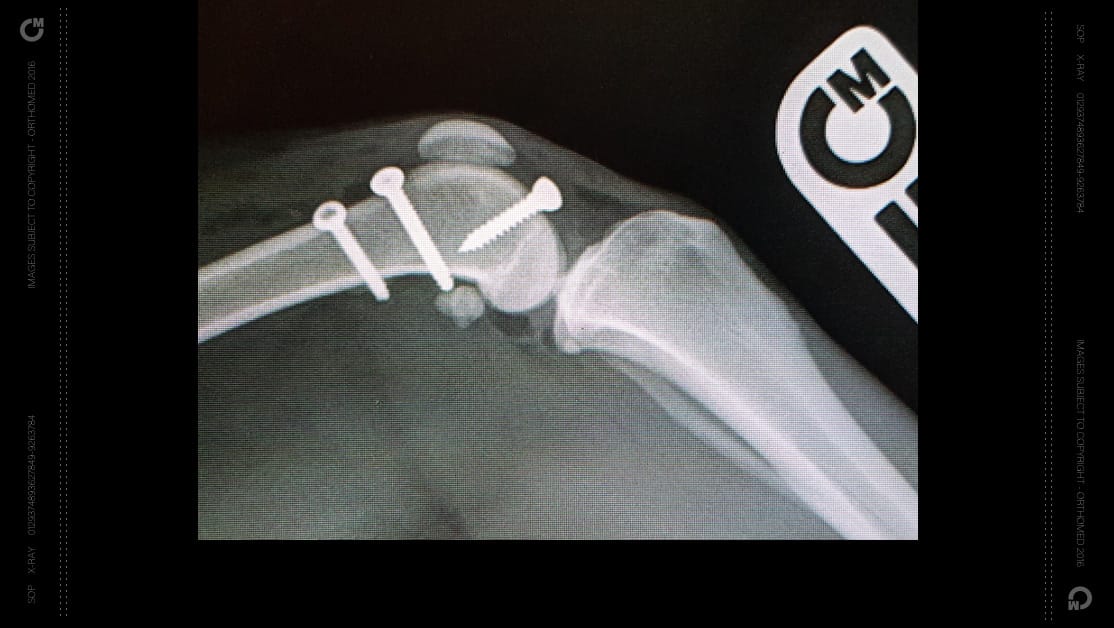

RidgeStop™ has been designed to provide surgeons with a cost effective alternative to sulcoplasty when carrying out procedures used to correct patella luxation. It uses a synthetic ridge held in place using standard cortical screws to build up the sides of the patella groove where it is insufficient or eroded due to degenerative conditions.

The ‘Ridge’, when correctly positioned acts as a barrier to prevent the patella slipping.

The aim of the surgery is to ensure the patella slides up and down within its groove without slipping to one side or the other, causing discomfort and lameness.

Unlike other procedures for this condition where the joint surface had to be cut, this is a much less traumatic procedure, as well as being more effective.

• Uses standard cortical bone screws

Each implant size has a corresponding drill guide, to ensure ideal placement of the implant. Depending on the implant size, they will require either two or three standard cortical bone screws, and the use of the drill guide allows not only ideal placement of the implant but also alignment of the divergent screw holes.